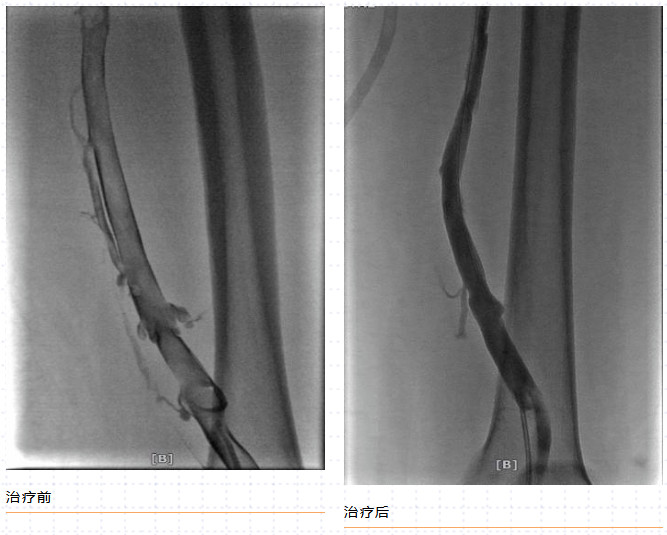

一經(jīng)確診,治療越早越好,這也可避免晚期的嚴(yán)重后遺癥。我們可以通過抗凝、溶栓、取栓、機械吸栓等辦法綜合處理血栓,即一站式完全微創(chuàng)的血管介入手術(shù),僅通過1~2處“針眼”,便可清除血栓,術(shù)后第二天即可出院。